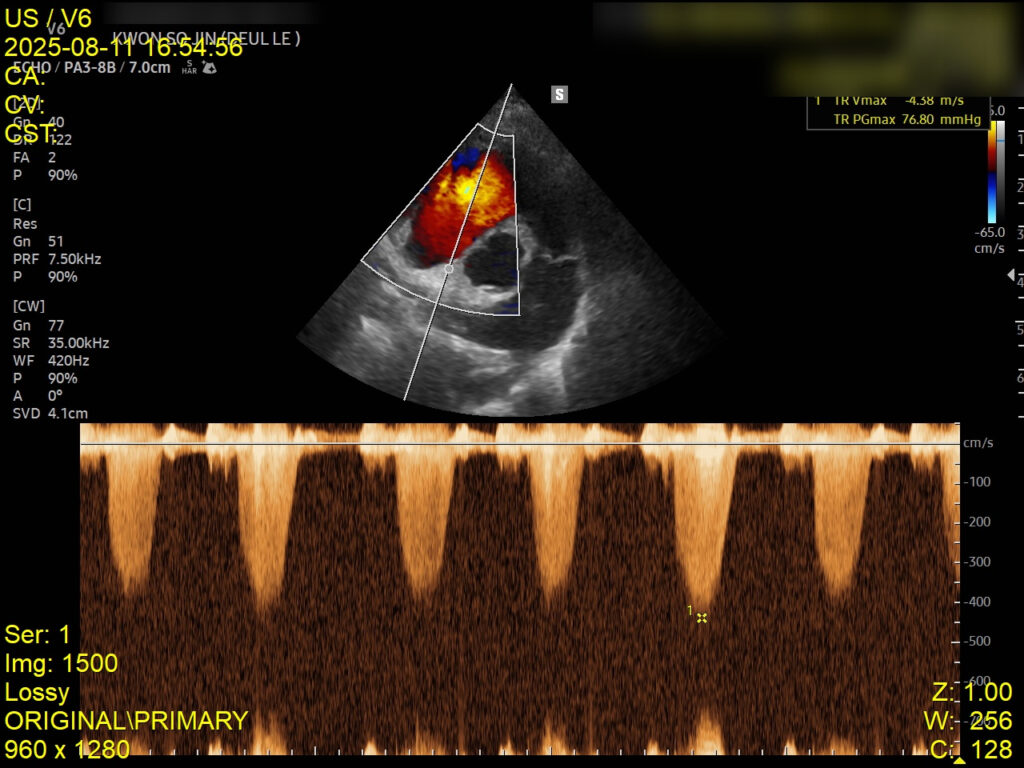

4. 심장초음파 검사

심장초음파에서는 좌심부전 소견은 없었으나, 폐성고혈압이 확인되어 이에 대한 약물 치료가 병행되었습니다. 이는 호흡곤란의 주 원인이 심장이 아닌 폐 자체의 염증성 병변임을 뒷받침하는 결과입니다.

심장초음파 검사 사진 / 출처: 강서 YD동물의료센터